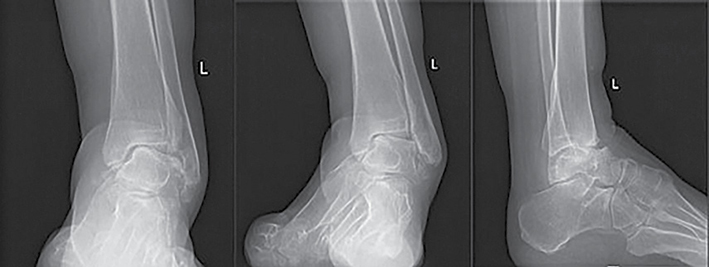

56 m. pacientė atvyko į Lietuvos sveikatos mokslų universiteto ligoninę Kauno klinikas (LSMUL KK) dėl metus trunkančio čiurnos ir pėdos skausmo bei deformacijos. Prieš metus pacientei diagnozuota CMT liga. Rentgeno vaizduose matyti kairės čiurnos cavovarus deformacija, šokikaulio panirimas, čiurnos sąnario artroziniai pakitimai, egzostozės po lateraline kulkšnimi. Kompiuterine tomografija nustatyta III stadijos čiurnos sąnario artrozė ir II stadijos subtalarinio sąnario artrozė. Objektyviai vertinant, pėdos plantarinė fleksija ‒ 20°, dorsifleksija ‒ 5°. Skausmas pagal skausmo skalę (VAS) įvertintas 8 balais (10 ‒ labai stiprus skausmas, 0 – skausmo nėra). Remiantis Europos čiurnos ir pėdos draugijos sukurta funkcijos vertinimo skale (EFAS), čiurnos ir pėdos funkcija įvertinta 4 iš 24 galimų balų (24 balai ‒ gera čiurnos ir pėdos funkcija). Taikant Amerikos pėdos ir čiurnos ortopedų draugijos (AOFAS) čiurnos ir pėdos funkcijos vertinimo sistemą, įvertinimas siekė 23 balus iš 100 galimų (100 balų – gera funkcija). Pacientei atlikta TTC artrodezė intrameduline vinimi, I padikaulio uždaro kampo osteotomija, koreguota padikaulio ašis, ji fiksuota rakinama plokštele ir sraigtais. Po operacijos rekomenduota 2 savaites laikyti koją pakėlus, 15 savaičių dėvėti čiurnos įtvarą, išėmus siūlus, dar 6 savaites dėvėti kompresinę kojinę, 12 savaičių neminti kojos. Po 10 savaičių pacientė turėjo atvykti kontrolinio vizito ir pradėti didinti krūvį. Reabilitacija pradėta praėjus 10 savaičių. Po metų rentgenologinėse nuotraukose matyti čiurnos ir subtalarinio sąnario ankilozė, kaulų ir vinies padėtis gera. Pagal VAS skausmas sumažėjo iki 2 balų, pagal EFAS jis vertinamas 18 balų, pagal AOFAS ‒ 66 balais.

1 pav. Kairės čiurnos ir pėdos tiesinė ir šoninė rentgenogramos prieš operaciją